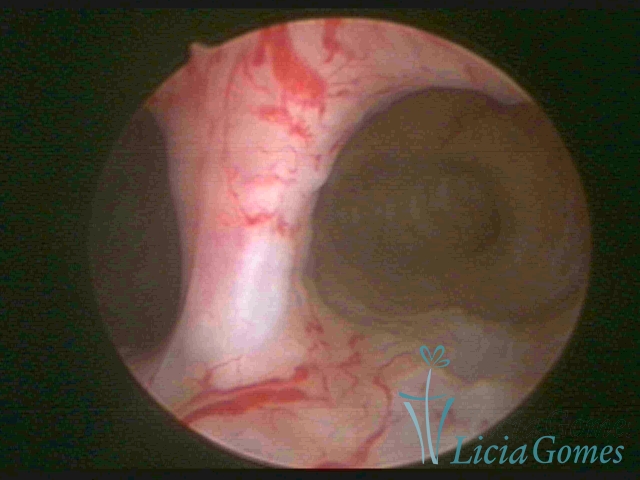

Unicornuate uterus

It presents a tubular cavity with an impaired intracavitary space, resembling the shape of a banana, whose the narrowest edge contains the tubal ostium. The endometrium is compatible with the menstrual cycle and the cervical canal is normal, in structure and trophism.